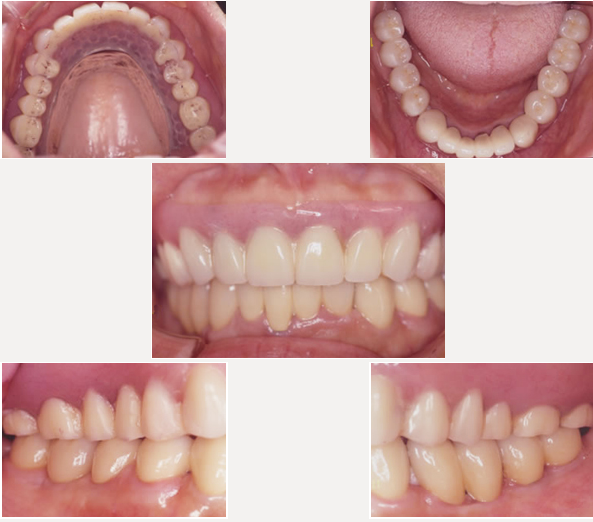

治療後

下顎の左右奥歯はインプラント治療により固定製に、弱っていた下の前歯はセラミック冠で固定しました。上顎は磁石義歯としました。しっかり咬む事ができました。